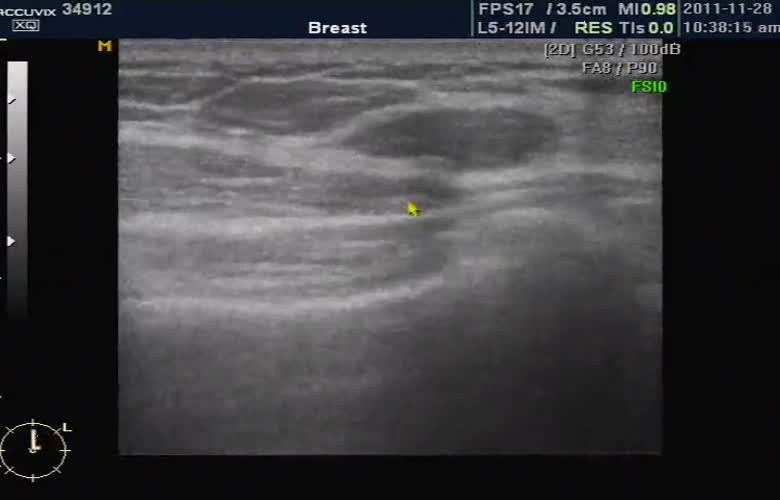

유방 초음파에서 본 결절의 모습입니다.

중심부에 검게 보이는 부분이 결절이며 이런 결절은 양성인 경우도 있고 악성인 경우도 있어서 크기나 모양 그리고 환자의 병력과 가족력 등을 감안하여 정밀 검사인 조직 검사 여부를 결정하게 됩니다.

왜냐하면 유방 초음파나 유방 X선 검사는 모두 결절이나 이상의 여부를 확인하는 것이지 최종적으로 악성인가 양성인가를 판다는 것은 아니기 때문입니다.

그러나 초음파에서 양성 종양처럼 보이는 경우에도 간혹 악성 종양인 경우가 있어서 원칙적으로는 유방의 조직 검사는 총조직 검사를 통하는 것이 일반적입니다.